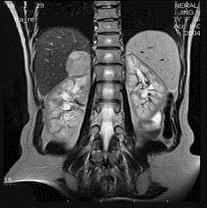

问题 男,31岁,体检时超声发现右肾上腺区病灶,MRI扫描如图所示,下列说法正确的是()

选项 A.右侧肾上腺区可见一类圆形病灶,与周围组织分界清楚 B.该病灶在T1WI为等信号,在T2WI为稍高信号 C.考虑为右侧肾上腺腺瘤 D.考虑为右侧肾上腺髓样脂肪瘤 E.考虑为右侧肾上腺嗜铬细胞瘤

答案 ABC